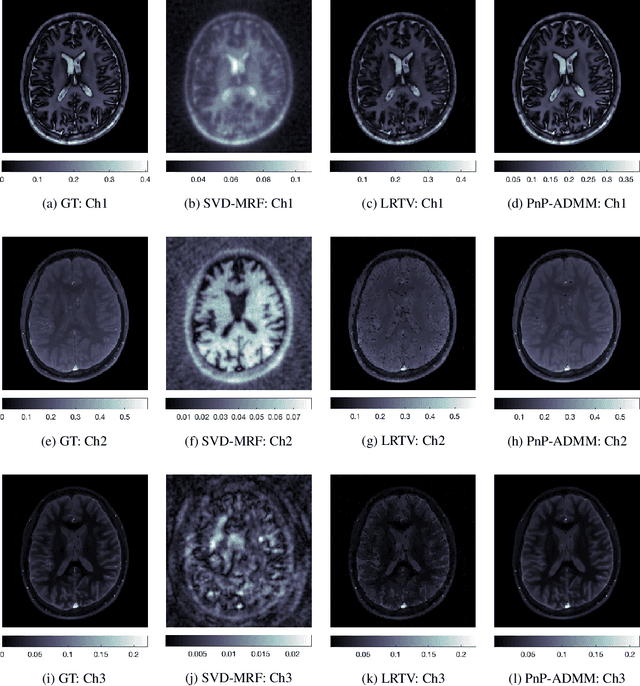

Abstract:Current spatiotemporal deep learning approaches to Magnetic Resonance Fingerprinting (MRF) build artefact-removal models customised to a particular k-space subsampling pattern which is used for fast (compressed) acquisition. This may not be useful when the acquisition process is unknown during training of the deep learning model and/or changes during testing time. This paper proposes an iterative deep learning plug-and-play reconstruction approach to MRF which is adaptive to the forward acquisition process. Spatiotemporal image priors are learned by an image denoiser i.e. a Convolutional Neural Network (CNN), trained to remove generic white gaussian noise (not a particular subsampling artefact) from data. This CNN denoiser is then used as a data-driven shrinkage operator within the iterative reconstruction algorithm. This algorithm with the same denoiser model is then tested on two simulated acquisition processes with distinct subsampling patterns. The results show consistent de-aliasing performance against both acquisition schemes and accurate mapping of tissues' quantitative bio-properties. Software available: https://github.com/ketanfatania/QMRI-PnP-Recon-POC

Abstract:Deep learning (DL) has recently emerged to address the heavy storage and computation requirements of the baseline dictionary-matching (DM) for Magnetic Resonance Fingerprinting (MRF) reconstruction. Fed with non-iterated back-projected images, the network is unable to fully resolve spatially-correlated corruptions caused from the undersampling artefacts. We propose an accelerated iterative reconstruction to minimize these artefacts before feeding into the network. This is done through a convex regularization that jointly promotes spatio-temporal regularities of the MRF time-series. Except for training, the rest of the parameter estimation pipeline is dictionary-free. We validate the proposed approach on synthetic and in-vivo datasets.